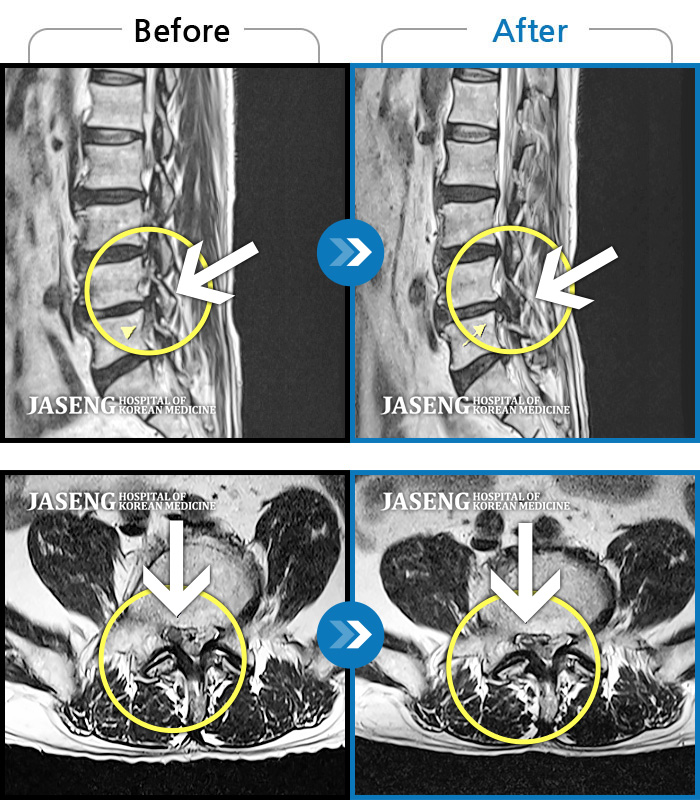

허리디스크

광주 · 김동은 원장

요추 5번과 천추 1번 사이에서 탈출된 디스크가 신경막을 압박

촬영시기

2017.08.26 ~ 2018.03.31

2020.01.23

조회수 5,097